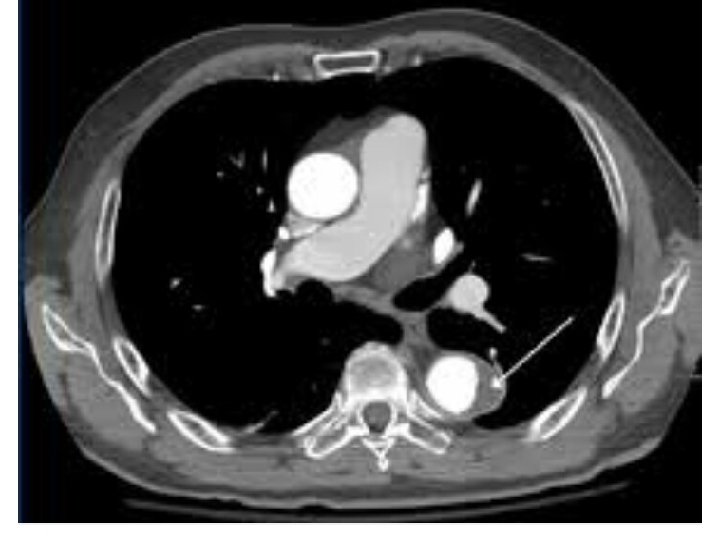

QUESTION 4 • A 63 yr old man was brought to emergency dept in cardiac arrest. he had a h/o HTN , DLP, CAD. pt c/o dizziness and dyspnoea prior to his syncope. his initial BP was 70/40 mm. Hg , HR 68 bpm , SPO 2 82% in RA.

------ • CAG Non obstructive epicardial coronary arteries and patent LAD 2 D ECHO Dilated Rt ventricle Rt sided heart catheterisation revealed RV pressure of 80/30 mm. Hg

Pulmonary angiogram disclosed filling defect s/o B/L pulmonary embolism